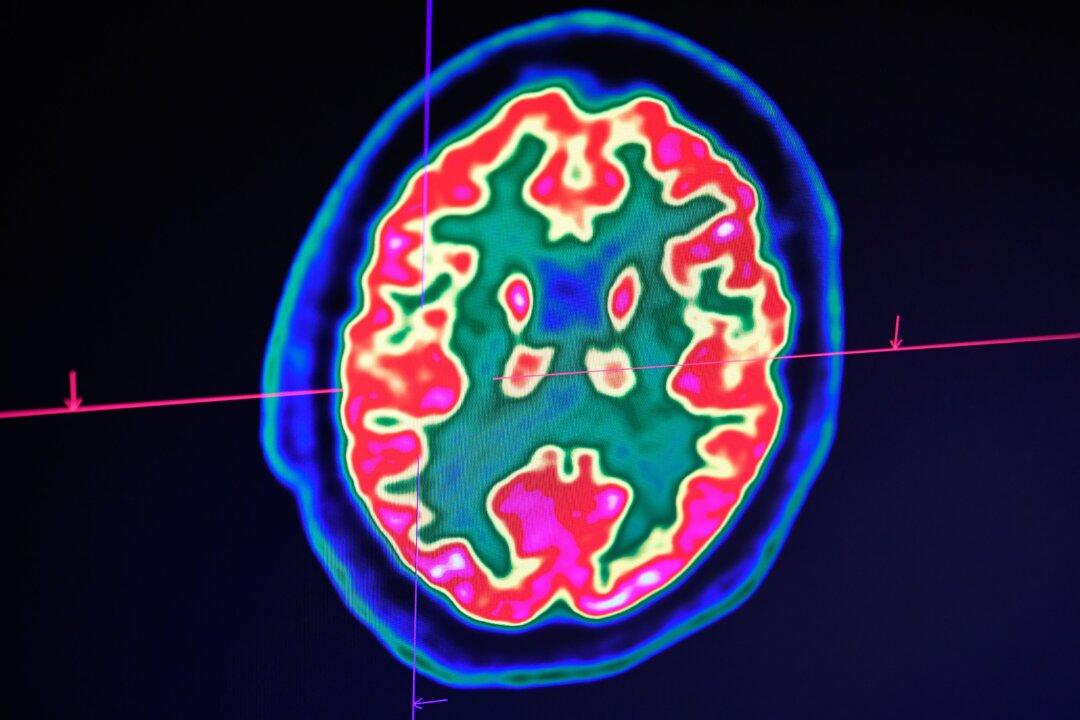

In this file image, a picture of a human brain taken by a positron emission tomography scanner, also called PET scan, is seen on a screen at the Regional and University Hospital Center of Brest in western France on Jan. 9, 2019. Fred Tanneau/AFP/Getty Images